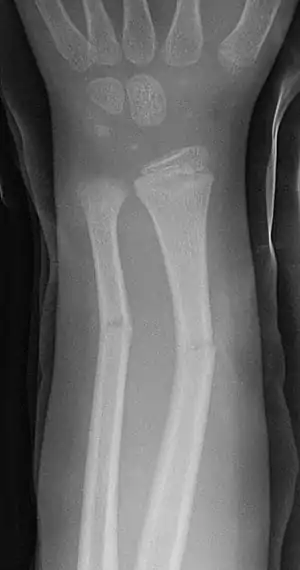

Greenstick fracture

| Greenstick fractures on X-ray. | |

A greenstick fracture is a fracture in a young, soft bone in which the bone bends and breaks. Greenstick fractures occur most often during infancy and childhood when bones are soft. The name is by analogy with green (i.e., fresh) wood which similarly breaks on the outside when bent.